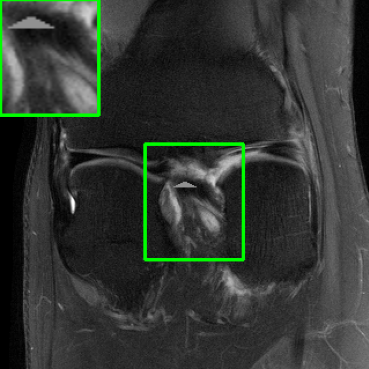

Results for the DIDN-based Reconstructor: To demonstrate adaptability to different network architectures, Table II compares reconstruction performance on the test set with the DIDN denoiser-based MoDL architecture. Average PSNR values with LONDN-MRI are compared to those with networks trained globally at different training set sizes. We ran only iteration of LONDN-MRI, where the reconstruction with a pre-trained (global) network was used to find neighbors. PSNR values for the oracle LONDN-MRI reconstructor are also shown. The overall performances with the DIDN-based architectures are better than with the UNet-based unrolled networks. The PSNRs for LONDN-MRI are consistently and similarly better than for the globally trained network across the different training set sizes considered, indicating potential for LONDN-MRI in improving state-of-the-art models. Fig. 6 visually compares reconstructions and reconstruction errors (in zoomed in region) for different methods. We can see that the LONDN reconstructors capture the original image features more sharply and accurately than the globally learned reconstruction.

| Ground Truth | Global | LONDN-MRI | Oracle |

| (1 iteration) | |||

![]() |

| PSNR = dB | PSNR = 34.15 dB | PSNR = 34.46 dB | PSNR = 34.54 dB |